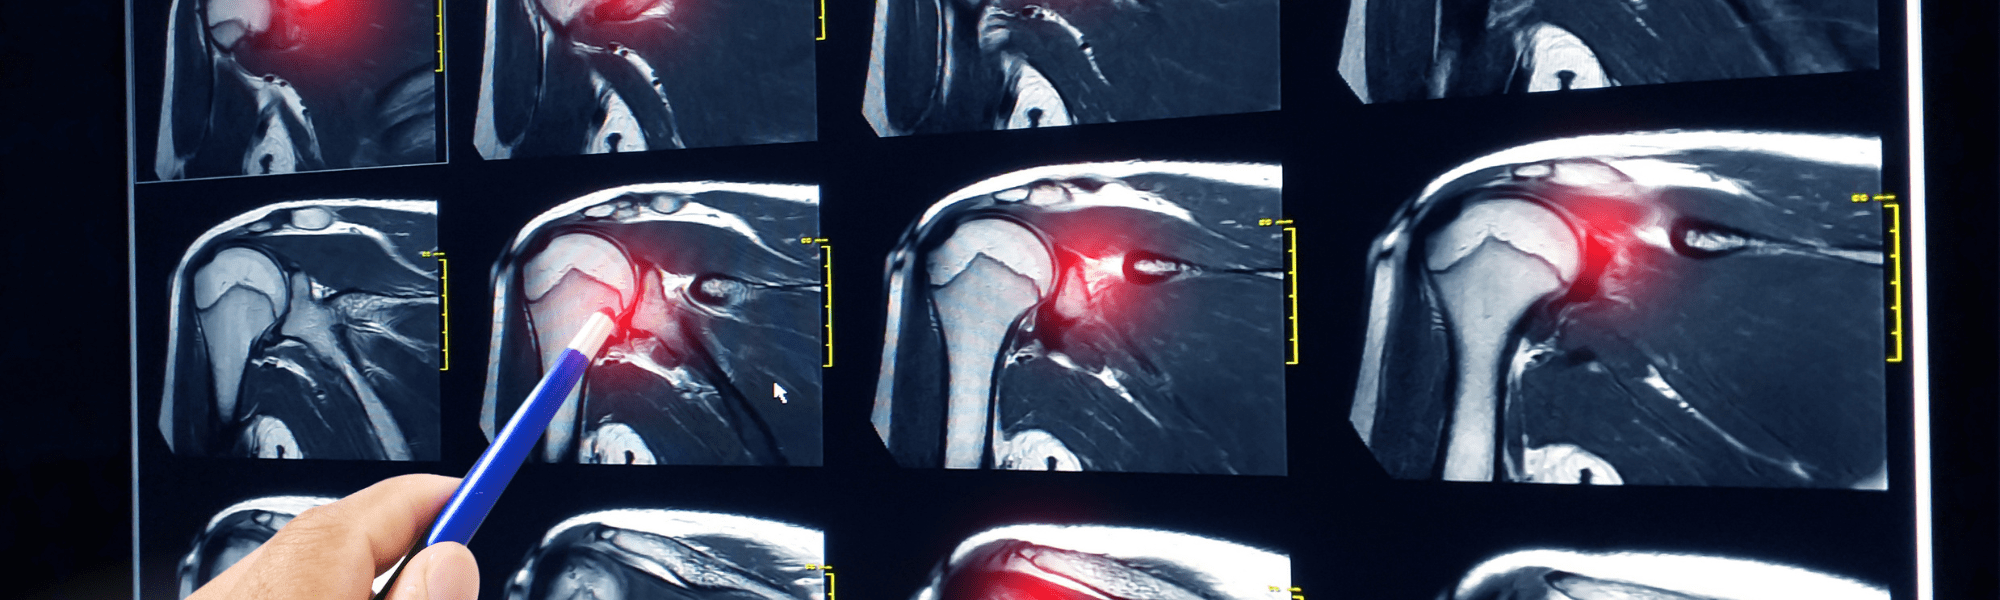

Mastering the Shoulder Exam Top Chiropractic Tests for Rotator Cuff and Impingement — ChiroUp Rotator Cuff Shoulder Chiropractor Learn about the causes, symptoms and diagnosis of rotator cuff injury, a common shoulder problem that affects the tendons and. What is the rotator cuff? A rotator cuff is a group of tendons (muscle. This helps relieve tension on the shoulders, reducing the pain associated with rotator cuff tears. First, the chiropractor will perform an adjustment to correct any misalignments. Rotator Cuff Shoulder Chiropractor.